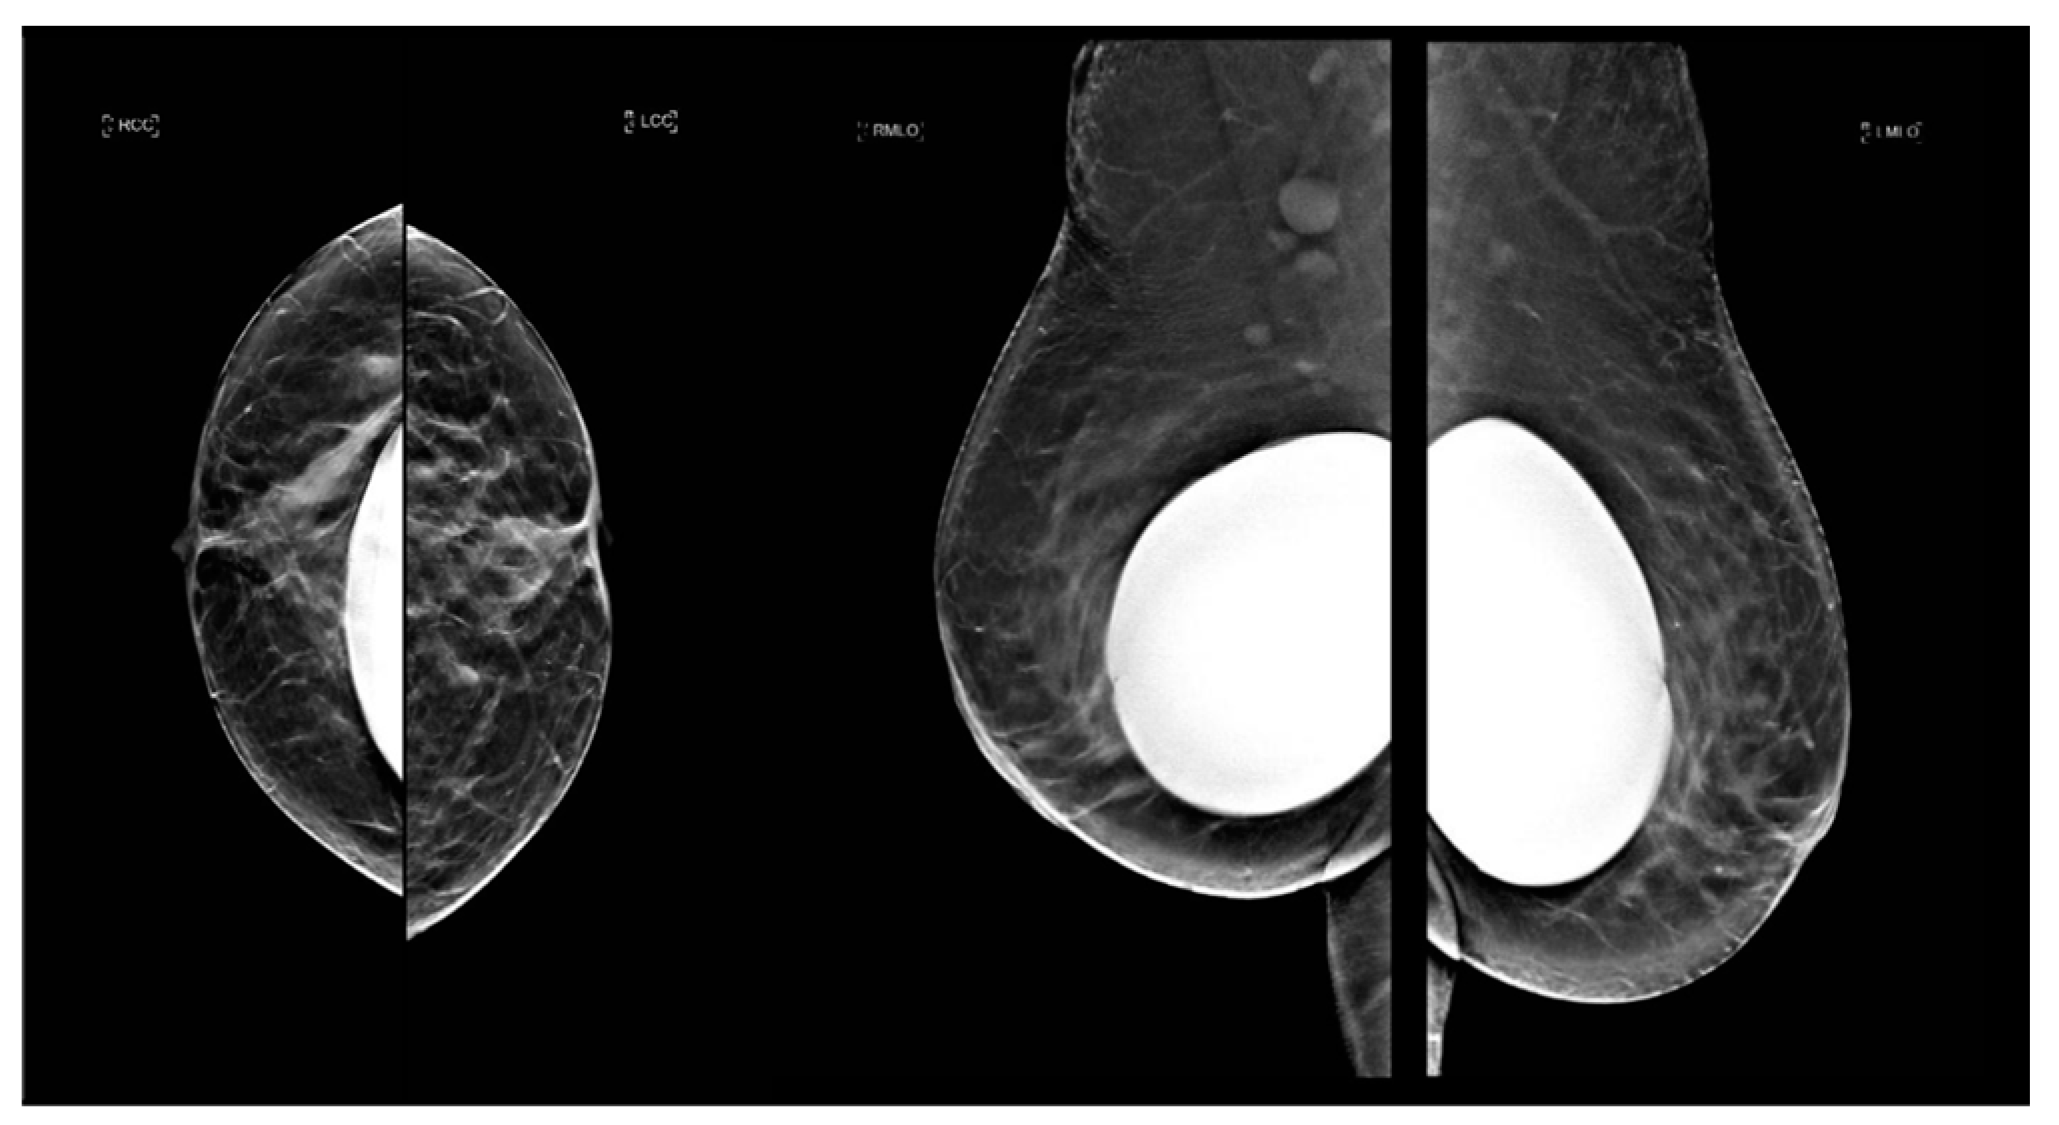

Comparison of Visual and Quantra Software Mammographic Density Assessment According to BI-RADS® in 2D and 3D Images

2.2. Image Acquisition

2.3. Software for Automatic Breast Density Assessment